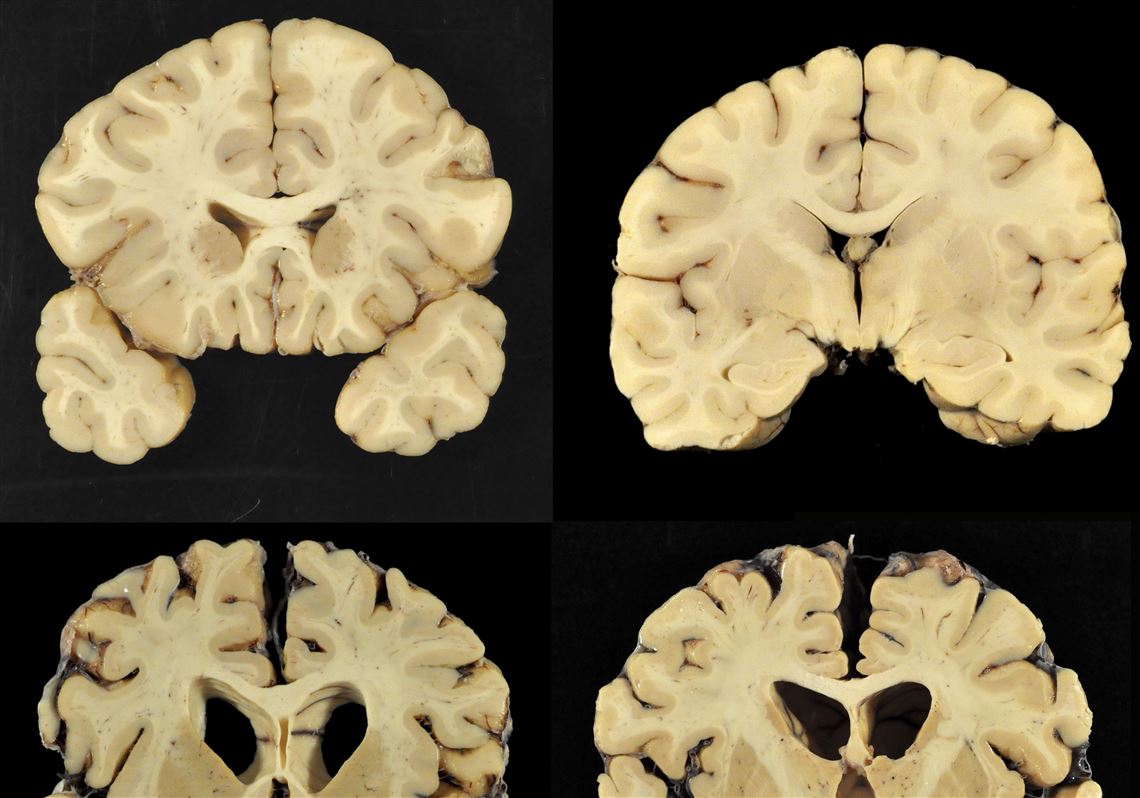

CTE is still a disease largely defined by its mystery. At this point in time, a definitive CTE diagnosis can only be made posthumously and there are no approved treatments for it.